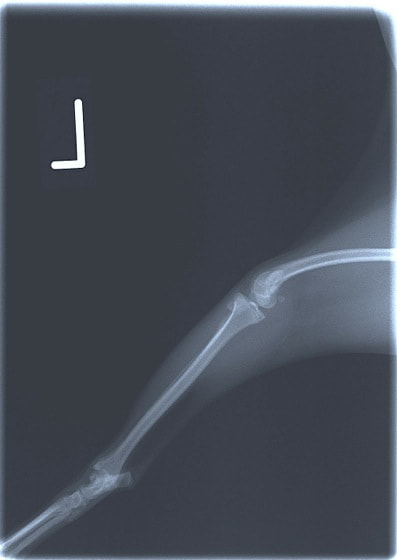

■ 症例20 ポメラニアン 8ヶ月 1.8kg

左右膝蓋骨脱臼 グレードⅢ

2ヶ月前から間欠的跛行が認められ、両膝の膝蓋骨脱臼整復術を行った。

手技は縫工筋及び内側広筋の解放、脛骨粗面の外側転位、滑車ブロック形造溝術、内外側関節包の縫縮を選択し実施した。

右側の膝蓋骨脱臼は上記手技で整復されたものの、左側はそれのみでは膝蓋骨が浮く様子が認められた。その為、PDS縫合糸にて膝蓋靱帯を1糸のみ縫合し、靱帯の縫縮を行った。

膝蓋骨脱臼は膝関節における膝蓋骨の内外側の脱臼と定義されるが、時として単純な内外の脱臼ではなく、膝蓋骨が大きく前方に浮き上がるように脱臼する場合がある。特にトイプードルやポメラニアンといった犬種に多く認められる。

内側脱臼に加えて前方への浮き上がりを矯正する為に、従来より脛骨粗面転移により膝蓋靭帯を外方と下方に引っ張り、固定する方法を選択する。膝蓋骨の前方への浮き上がりが軽度の場合は、従来法ではなく関節包の縫縮で対応していた。しかし、一部の症例で膝蓋骨の動きが悪くなり伸展機構が円滑に機能せずロボット様歩行になるケースがあった。

その為、膝蓋靭帯自体を縫縮する方法を採用した。この方法により、膝関節の伸展機構を妨げず膝蓋骨の軽度の浮きを矯正することが可能となった。

本症例の経過は良好である